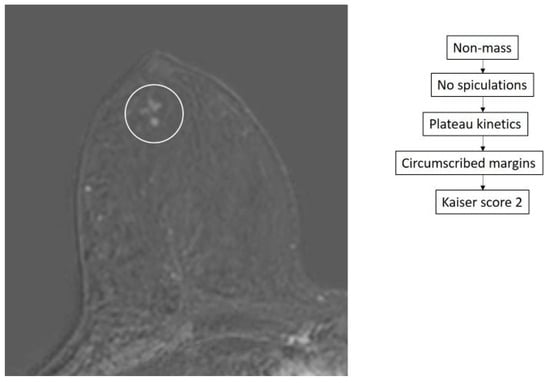

- Dietzel, M.; Baltzer, P.A.T. How to Use the Kaiser Score as a Clinical Decision Rule for Diagnosis in Multiparametric Breast MRI: A Pictorial Essay. Insights Imaging 2018, 9, 325–335. [Google Scholar] [CrossRef] [PubMed]